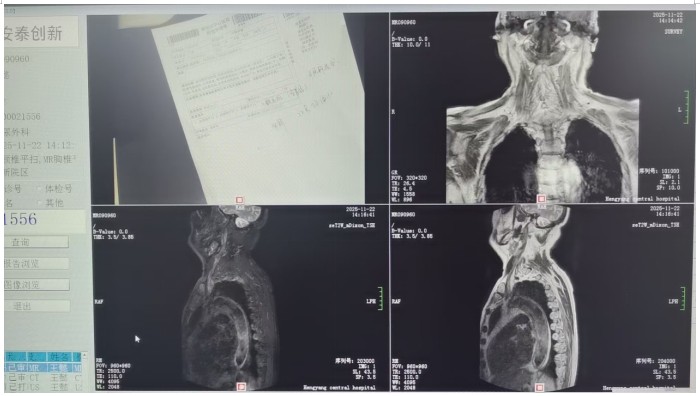

馬子芳團(tuán)隊(duì)詳細(xì)詢問患者病史和治療情況后,對患者進(jìn)行了相關(guān)輔助檢查,初步診斷患者為神經(jīng)源性膀胱??紤]到老人82歲高齡、基礎(chǔ)疾病多等情況,團(tuán)隊(duì)多次組織病例討論,與患者及家屬充分溝通,最終決定為患者實(shí)施微創(chuàng)、可逆的骶神經(jīng)刺激器植入術(shù)進(jìn)行治療。很快,馬子芳團(tuán)隊(duì)老人實(shí)施了一期骶神經(jīng)調(diào)控電極植入術(shù),術(shù)中精準(zhǔn)定位,成功穿刺骶3神經(jīng)孔,術(shù)中測試各位點(diǎn)的運(yùn)動應(yīng)答、感覺應(yīng)答明顯,無不良反應(yīng)。